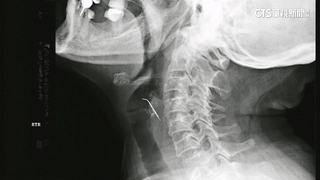

主播:「女童在醫院接受緊急治療,下午6點左右恢復脈搏。」南韓忠清北道一名2歲9個月大的,女童30日下午掉進一公尺深的水溝,失去心跳呼吸,急救後恢復生命跡象,院方研判女童必須轉到大醫院開刀,但聯絡了9家醫院都以沒有病床的理由拒絕,儘管最後有一家醫院願意幫女童開刀,但女童來不及轉院就死亡。

主播:「女童在恢復脈搏1小時後,再次陷入心跳停止狀態,最後被判定死亡。」根據韓聯社報導,尹錫悅政府堅持要擴招2000名醫大生,醫界認為這無法解決,低薪和高工時人手分配不均問題,引發大批醫師不滿罷工辭職。民眾:「令人擔憂小孩子跟大人不同,小孩有很多緊急狀況。」